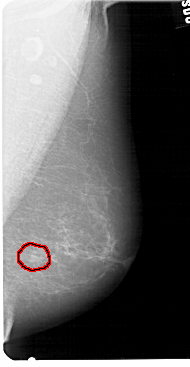

A_1428_1.LEFT_MLO

LEFT_MLO LINES 5491 PIXELS_PER_LINE 3001 BITS_PER_PIXEL 12 RESOLUTION 43.5 NON_OVERLAY

FILE: A_1428_1.RIGHT_MLO.OVERLAY

TOTAL_ABNORMALITIES 1

ABNORMALITY 1

LESION_TYPE MASS SHAPE LOBULATED MARGINS ILL_DEFINED

ASSESSMENT 4

SUBTLETY 4

PATHOLOGY BENIGN

TOTAL_OUTLINES 1

BOUNDARY